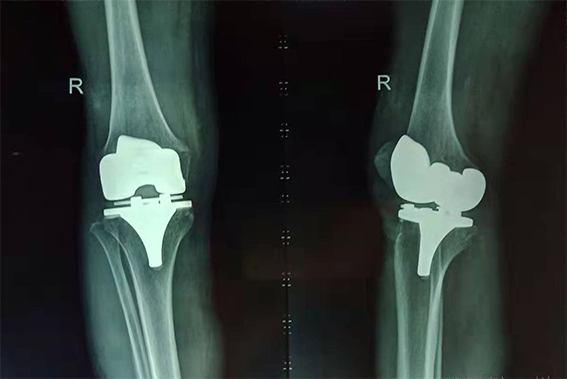

經(jīng)過醫(yī)院專家組聯(lián)合會(huì)診,劉鴻程主任決定采用取右膝正中切口,依次切開皮膚、皮下組織、膝關(guān)節(jié)、顯露股骨遠(yuǎn)端及脛骨近端,松解內(nèi)外側(cè)軟組織,根據(jù)術(shù)中情況決定脛骨及股骨截骨平面,安裝假體;縫合關(guān)節(jié)囊腫、皮下組織及皮膚。手術(shù)過程中沒有任何肌肉或肌腱的切斷,對(duì)肌肉無損傷,術(shù)后發(fā)生假體脫位的風(fēng)險(xiǎn)低,從而可以早期康復(fù)。

吳奶奶術(shù)后右膝X光片

“頭天做了手術(shù),第三天就能下地走路了,真是太神奇了!這給子女們減輕了不少負(fù)擔(dān)。”吳奶奶高興地說。目前她正在醫(yī)生的指導(dǎo)下,進(jìn)行康復(fù)訓(xùn)練。